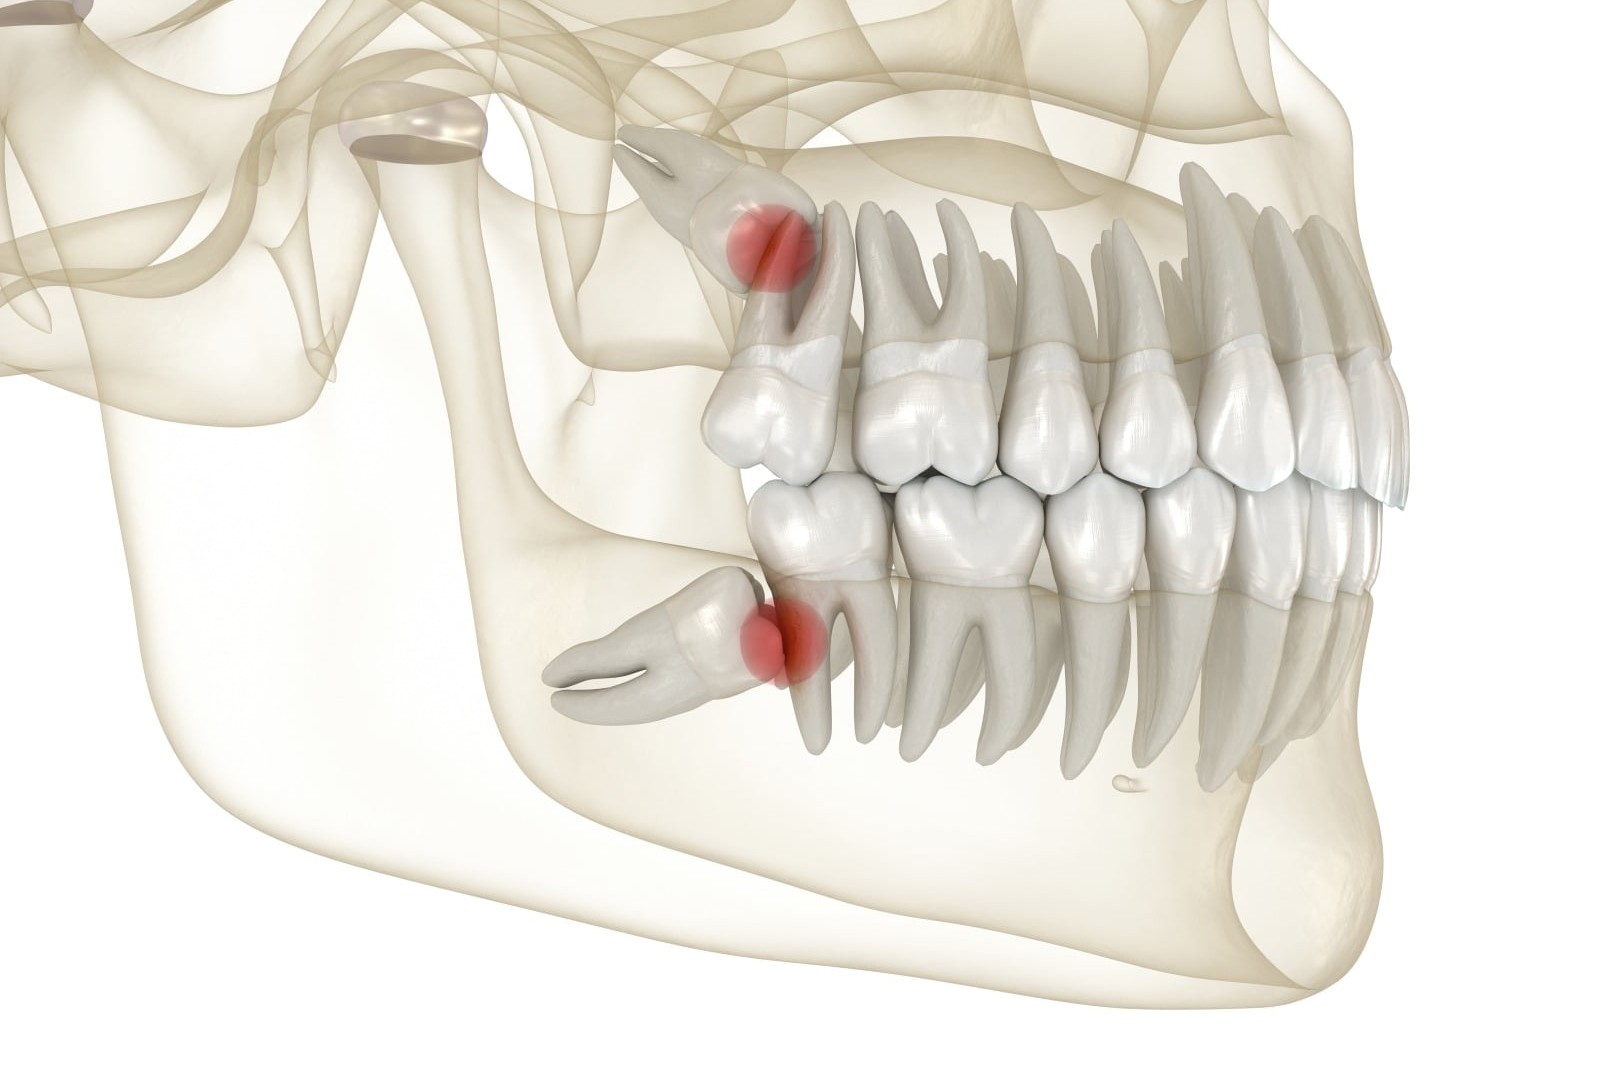

IMPLANTOLOGIA

Il tuo miglior investimento.

- Per sostituire uno o più denti

- Anche con innesti ossei o rialzo di seno mascellare